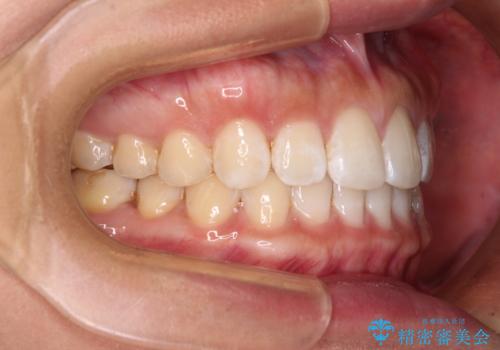

【モニター】前歯のすきっ歯をインビザラインで改善

- 上顎前歯の隙間と口元の突出感を気にして来院された患者様です。

高校生の時に行った矯正治療の後戻りであり、歯列不正は軽度であったので、インビザラインにて治療を行うこととしました。

すきっ歯はあっという間に後戻りを起こすので、可及的に後戻りを防止するために、上下前歯部を舌側からワイヤーで固定しています。

通常は下顎前歯のみに行っていますが、空隙歯列弓では上顎でも行っています。